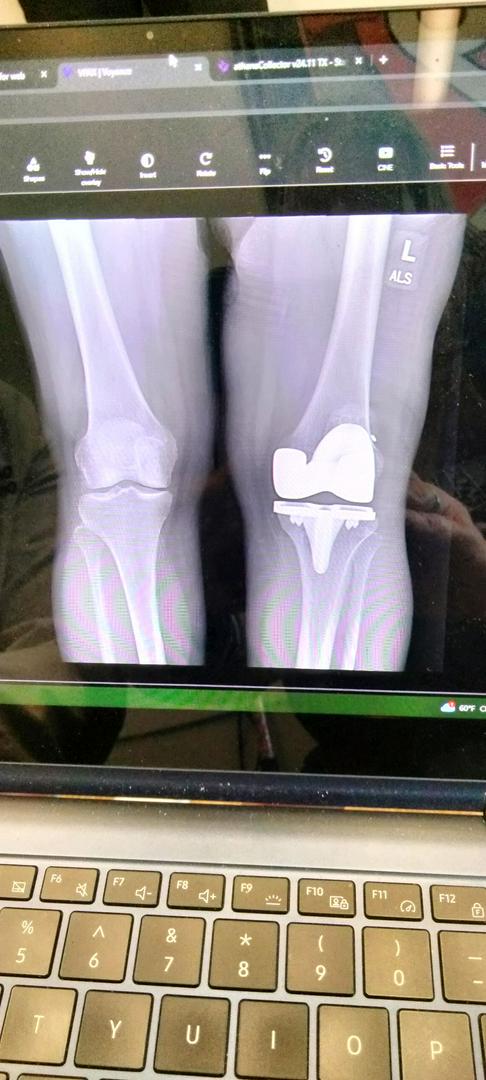

Knee! I've had both of mine done!

Since we're all sharing our x-rays I figured I'd share mine. I must say that PT was rough! I only did 8 weeks of it at home, and I never did any outpatient PT, so I do still have a lot of pain in the new knee. I've decided against doing the other knee, too painful!

knee

knee replacement thats the kneecap

I've had both my knees totally replaced. One in 1999 and the other in 2001. They say a replacement knee only last 12 to 15 years before you would need to have it replaced again. So far I've lucked out. I had a fantastic surgeon. It is now 2026 and I still have both knees and haven't needed the 2nd replacements. I don't have pain in either one of them. Just a little stiffness getting up if I sit too long. I obtained my surgeon through Cleveland clinic sports medicine. The doctor I had is now retired. His name was Doc Brooks. I thank him everyday for a job well done. If I didn't have the surgery, I would have been in a wheelchair right now.

Looks like the prosthetic component for the medial condyle of the femur and it’s quite possible that it’s part of a Total Knee Arthroplasty.

This is a partial knee joint replacement. I help put them in everyday except Friday Saturday and Sunday..Upper part.

This xray is revision surgery repair of snapped patellar tendon after total knee replacement. Recovery after this surgery required 8 weeks in a full leg cast (non weight bearing) miserable surgery, recovery and physical therapy!